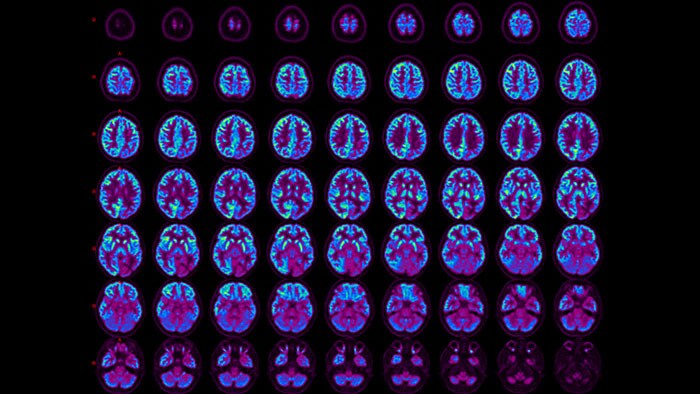

Aiding in the differential diagnosis of dementia

The NM NeuroQ 3.75 application is designed to help clinicians perform a quantitative analysis of FDG-PET brain scans. The application compares the regional brain activity in an individual scan to activity values derived from a group of asymptomatic control subjects. It analyzes the distribution of FDG-PET in individual scans, as sometimes it’s hard to detect differences between two PET scans on the same patient taken at different points in time.

Assessing Amyloid plaque

The NM NeuroQ Amyloid analysis tool is designed to help clinicians to assess the presence or absence of Amyloid plaque in the brain. Provides quantitative analysis tools for Brain PET scans using NeuraCeq or Amyvid agents.